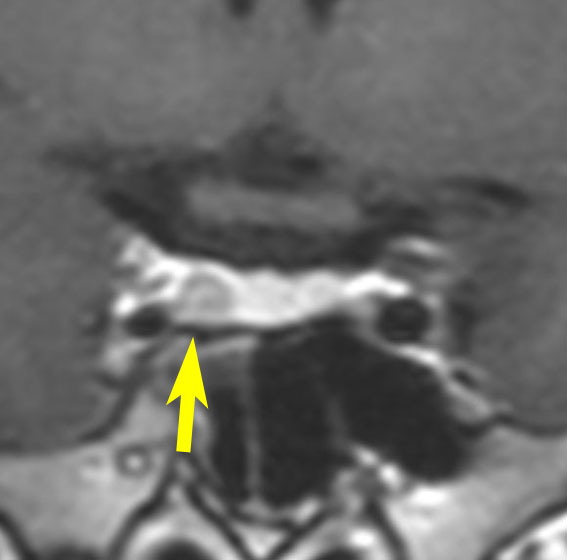

とても小さな腫瘍(微小腺腫) microadenoma

日本で汎用されているものでは最も解像力が高い3テスラMRIで撮影された,ガドリニウム増強像です。左側の画像では下垂体の大きさと形は正常に見えます。画像を調整すると,下垂体の内部,右端(黄色の矢印の先)に6mmくらいの小さな腺腫がみつかりました。MRIの性能がよくなったことによって数mmの小さなものも診断できるようになりました。